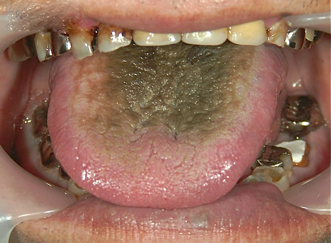

70代の男性。主訴は「最近、舌が黒くなってきた。なんか怖い病気になってないか心配。大丈夫かな?」でした。

Dr:「これは、黒毛舌とよばれているものです。ピリピリするともおっしゃられていましたが、決して怖い病気ではありません。舌が黒色に着色したものです。原因は、抗生物質(抗生薬)やステロイド薬の長期服用により、口の中の細菌群の変化によるものです。(実際、この患者様も、抗生薬を2ヶ月ほど飲み続けておられました。)薬の服用を止めれば、2〜3週間で治まりますので、内科の先生にご相談して下さい。」とお答えしました。